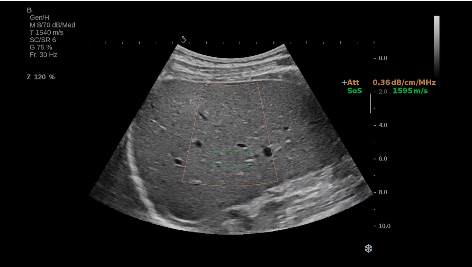

法國聲科影像(SuperSonic Imagine,SSI. Euroniex:FR0010526814)近日發(fā)表公告,宣布其研發(fā)的新一代“極速”超聲成像平臺(UltraFast Imaging),首次實現(xiàn)了肝臟的多項超聲定量評估新指標(biāo)同步檢測,包括:Att PLUS,SSp PLUS和Vi PLUS等,基本涵蓋肝臟相關(guān)病理變化指征的如纖維化、脂肪變、炎癥等。據(jù)悉,此多項新技術(shù)新將搭載于新Aixplorer系列E超系統(tǒng)。